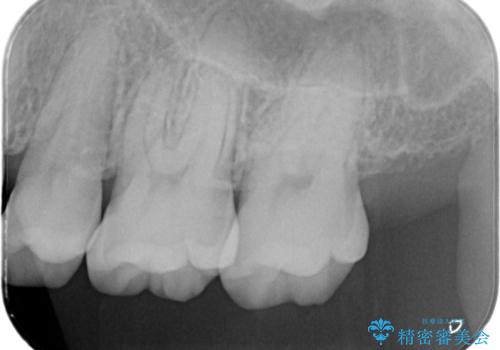

- 定期的にクリーニング(保険適応)に通って頂いている患者さんです。歯周ポケットが4ミリあったため歯茎を開いて歯石を除去するためにオープンフラップ術を行うことにしました。

歯周ポケットがそれほど深くない患者さんでしたが、いざ歯茎を開いてみるとそこにはたくさんの歯石がありました。もし歯周ポケットが4ミリだからと言って放置していれば数年後には、沢山の骨が無くなっていたことが予期出来ます。現段階で歯茎の下にある歯石を除去することにより骨が無くなることを予防する事が出来ました。